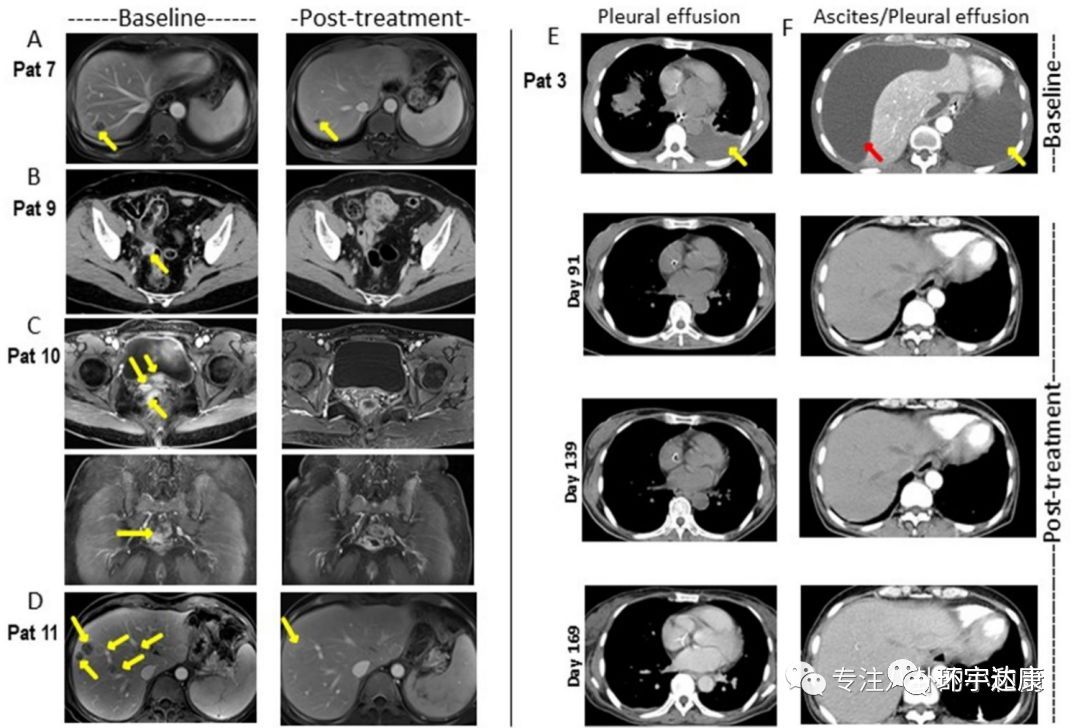

典型病例

这两例患者生存时间分别是20.5个月(图P13)和44.2个月(图P3),其中一例疾病稳定的患者至今生存期将近4年!

图片